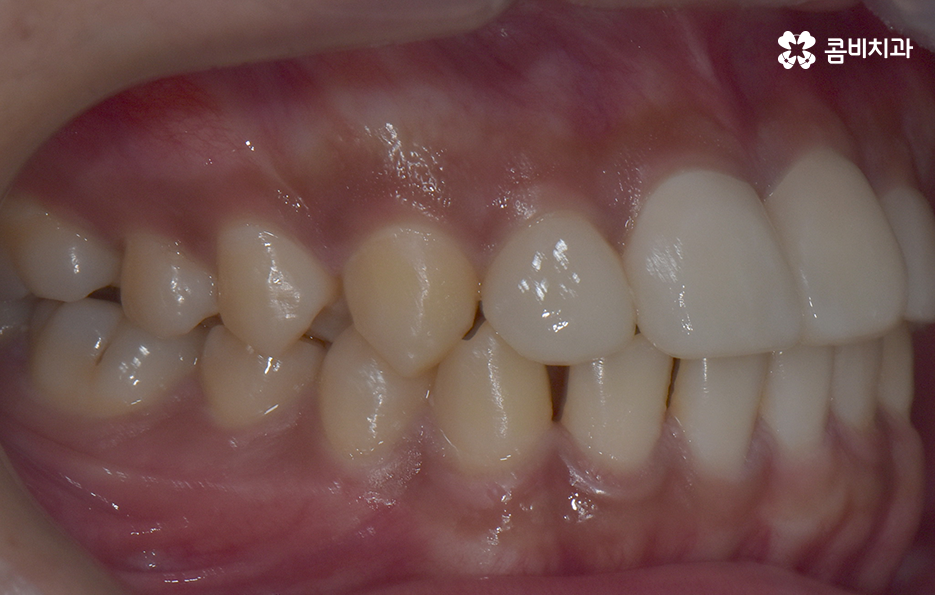

그나마 다행인 점은 앞니만교정을 하더라도 치아의 교합이나 골격적인 부분, 얼굴형 등에 있어서 큰 지장은 없던 경우였는데요. 물론 아랫니가 다소 벌어져 있기 때문에 전체교정을 하면 더 좋은 결과를 얻을 수 있었겠지만 환자분의 니즈에 있어서 앞니만교정을 빠르게 원했던 사례이기 때문에 앞니 부분의 과잉치 발치 후 앞니만교정을 부분적으로 진행했어요

과잉치로 인해서 치아 배열이 전체적으로 불규칙해지는 경우도 있고 돌출입의 형태로 나타는 경우도 있지만 다행이도 입술라인이나 얼굴형에 있어서 돌출은 크지 않은 상태였다는 점도 앞니만교정을 해도 어느정도 좋은 결과를 낼 수 있던 케이스로 볼 수 있어요

과잉치로 인해 말그대로 치아의 정상 범위 이상으로 치아가 배열되기 때문에 다른 치아의 배열에도 악영향을 주는 경우가 많지만 위 환자분의 케이스의 경우에는 치열 자체는 전체적으로 가지런한 편이라는 점과 특히 턱뼈가 넓은 편이라는 점에서 전체교정을 하지 않았어도 환자분이 원하는 치료의 목표는 달성할 수 있었어요

치아교정 기간은 각 환자분들에 따라 천차만별이기 때문에 정확하게는 각 환자분들의 상태를 직접 확인해봐야 하며 누구나 앞니만 부분적으로 교정이 가능한 것은 아니기 때문에 정밀검진이 우선적으로 필요하며 위 환자분의 경우에는 과잉치를 발치하고 교정기 장착 후에 약 6개월 정도가 지나서 교정기를 떼어낼 수 있었어요